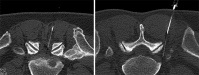

Spinal injection procedures can be performed blindly or, more accurately, with fluoroscopic or computed tomography (CT) guidance. Radiographic guidance for selective nerve root blocks and epidural injections allows an accurate needle placement, reduces the procedure time and is more secure for the patient, especially in patients with marked degenerative changes and scoliosis, resulting in a narrowing of the interlaminar space. Limiting factors remain the availability of scanners and the radiation dose. Interventional CT scan protocols in axial CT-acquisition mode for epidural and periradicular injections help to limit the radiation dose without a significant decrease of image quality. The purpose of this retrospective study was to analyze the effective radiation dosage patients are exposed during CT-guided epidural lumbar and periradicular injections. A total amount of n=1870 datasets from 18 months were analyzed after multiplying the dose length product with conversion factor k for each lumbar segment. For lumbar epidural injections (n=1286), a mean effective dose of 1.34 mSv (CI 95%, 1.30-1.38), for periradicular injections (n=584) a mean effective dose of 1.38 mSv (CI 95%, 1.32-1.44) were calculated.